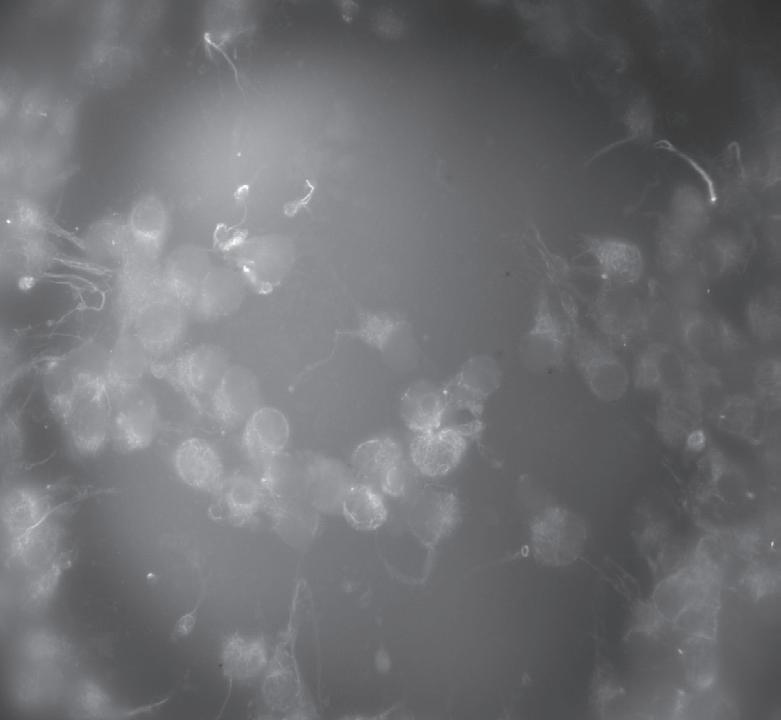

Much of the research at the CHR has focused on why some oocytes are fully mature after trigger and why others fail to either initiate or complete the maturation process. Dr. Albertini has spent much of his career trying to understand the fascinating dialogue that exists between the oocyte and cumulus cells and here in this image is an example of one of his CHR research projects. Looking down on the surface of a human oocyte, many cumulus cells can be seen and using special staining techniques. Cumulus cells “reach out and touch” the oocyte using fine extensions referred to as Transzonal Processes or TZPs for short. TZPs serve as conduits for supplying the oocyte with both nutritional and informational molecules that tell the oocyte to mature and prepare for fertilization, key elements in the underlying biology that will dictate which oocytes go on to develop as an embryo-or not.